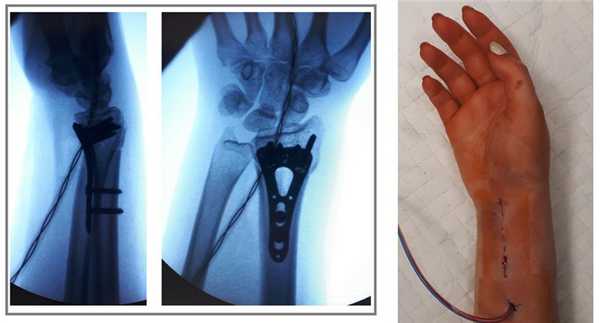

Пациент Х. Травма в быту, упал на бордюрный камень, получил закрытый перелом обеих костей правого предплечья со смещением, разрывом дистального радио-ульнарного сочленения. Обратился в РТП, выполнены рентгенограммы. Наложена гипсовая лонгетная повязка.

Пациент обратился в К+31, учитывая характер перелома пациенту предложено оперативное вмешательство.

Интраоперационная оценка стабильности дистального радиоульнарного сочленения.

Выполнен остеосинтез обеих костей правого предплечья метафизарными пластинами 3,5 мм, фиксация дистального радио-ульнарного сочленения винтом.

Внешний вид конечности после операции, угловая деформация устранена. Сегмент конечности стабилен, движения в локтевом и лучезапястном суставах не ограничены, ротация предплечья ограничена из-за наличия позиционного винта, который будет удаляться через 6 недель.

Реннтгенограммы после операции.